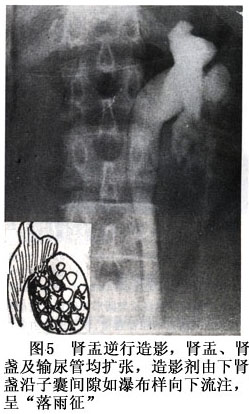

2.X线 KUB平片可见肾影增大,有凸出肾缘的肿块轮廓。有时可见肿块边缘线状钙化阴影。排泄性及逆行尿路造影示肾盂、肾盏受压变形、移位,肾盏漏斗部变细、拉长。当包囊破入肾盏,则造影剂溢入囊内显示多个圆形充盈缺损,造影剂沿子囊间隙流注而呈落雨样征象。同时可见患肾积水、显影不良或不显影(图1~7)。 医学百科网 | YxBaike.Com